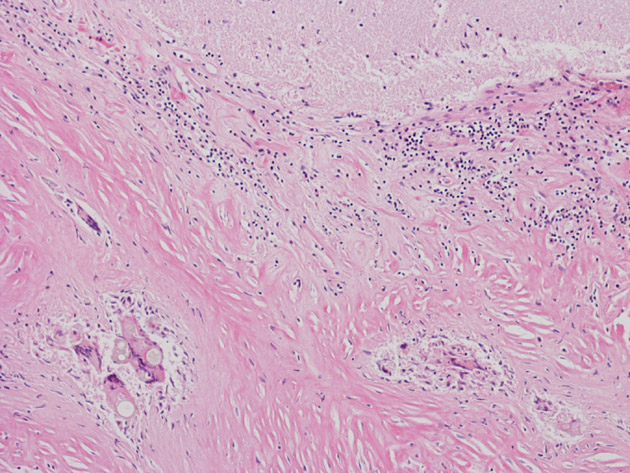

Hematoxylin & eosin

Area 2: The granulomas are composed of histiocytes in concentric arrangements forming nodules. At the center of the granulomas are mulitnucleated ginat cells containing the fungus.

Area 4: In this image, you can see numerous granulomas (arrow) lining along the dura.